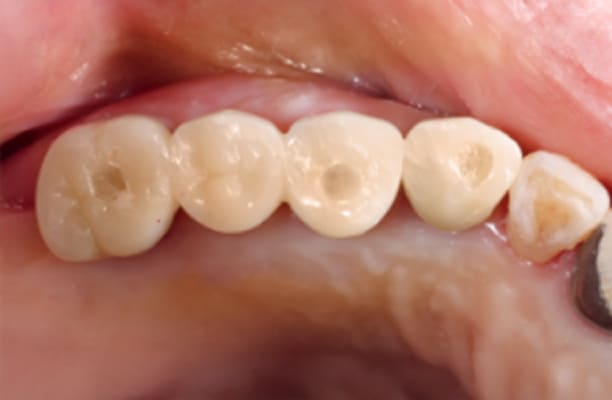

13+ 年

-

种植体植入:2012 年 9 月 -

最终修复体:2013 年 1 月 -

随访:13 年(2025 年 1 月)